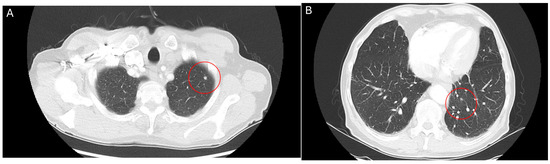

Figure 2.

CT thorax scan, 12 July 2024, after 6 weeks treatment with belzutifan: regression of pulmonary metastases for the left-upper (A) and lower lobe (B).